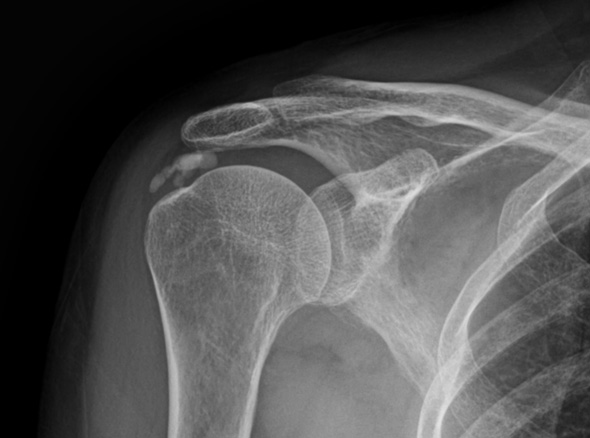

정확한 진단을 통하여 무조건 비수술적 치료, 무조건 수술적 치료가 아니라

환자의 상태에 맞는 최선의 치료를 선택할 수 있게 합니다.

어깨 힘줄 내부에 칼슘 석회가 침착되어 힘줄의 손상과 함께 통증을 유발하는 질환입니다.

석회화건염은 어깨 질환중 갑작스럽게 통증이 나타나는 경우가 많이 있습니다.